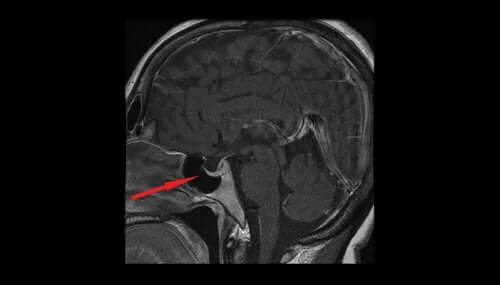

Gli esami più importanti per la conferma della diagnosi sono il campo visivo, la tomografia computerizzata (TC) e la risonanza magnetica cerebrale.